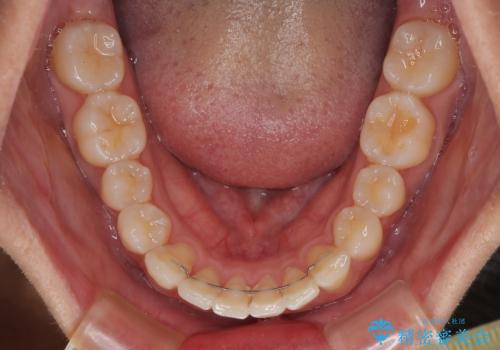

前歯のデコボコをインビザラインで綺麗に改善

- 上下前歯のデコボコとクロスバイトを気にして来院された患者様です。

インビザラインを用い、IPR(歯と歯の間を削る)と歯列全体を拡大させることで、歯並びを整えていくこととしました。

毎日22時間の装着時間を徹底してくださったのですが、左右ともに臼歯が咬合しなくなるという、インビザライン独特の症状が強く長く続いてしまい、終了するまでに長期間を要してしまいました。